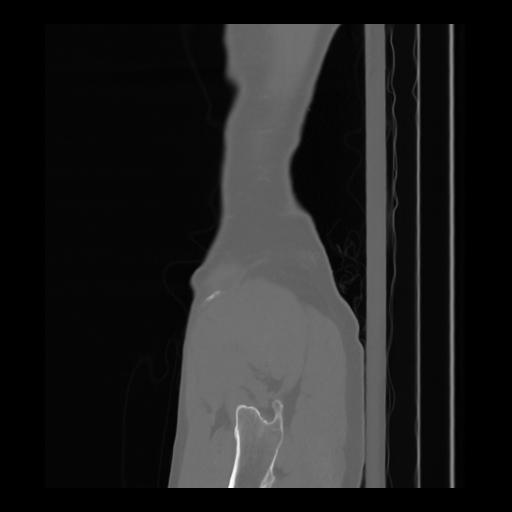

36 CUERPO,CE,Sagittal,3.000,CUERPO,Sagittal,